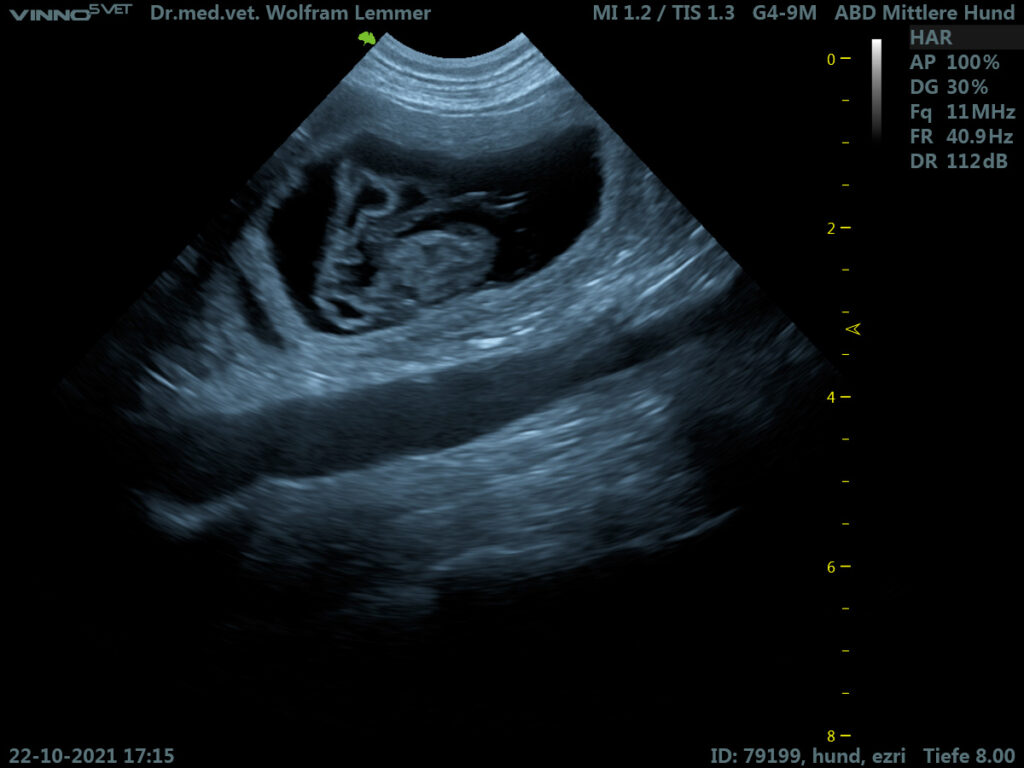

Die Ultraschalluntersuchung am 22. Oktober zeigte mehrere gutentwickelte Föten, die in ihren Fruchtblasen hüpften. Die kleinen Herzchen schlagen zu sehen, ist immer wieder ein ergreifender Moment.